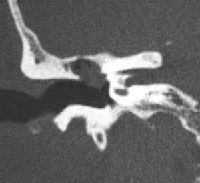

¿Qué es un colesteatoma? ¿Cómo puede tratarse?

El colesteatoma es un tumor benigno del oído, que afecta inicialmente al tímpano y a los huesecillos (martillo, yunque y estribo). Está formado por un cúmulo de piel que crece de manera desordenada y progresiva.

Su tratamiento es siempre quirúrgico, y consiste en la timpanoplastia, intervención en la que, mediante microcirugía, se extirpa completamente el colesteatoma. El resultado (exitoso en un 90% de casos) será siempre mejor cuanto más precozmente se intervenga.

Además de la extirpación completa del colesteatoma, la intervención persigue conservar al máximo la audición existente, y si es posible la recuperación de la ya perdida, mediante la reconstrucción de los huesecillos del oído medio (osiculoplastia), aunque no siempre es posible.